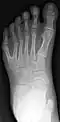

Radiographie de face du pied gauche d'un enfant atteint de polydactylie.